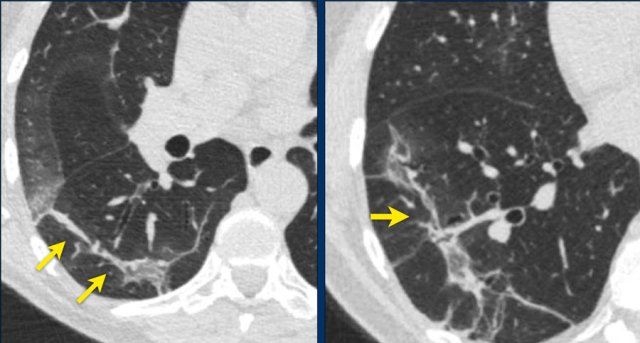

A typical finding in the area of ground glass is widening of the vessels (arrow).

Another common finding in the areas of ground glass is traction bronchiectasis (arrows).